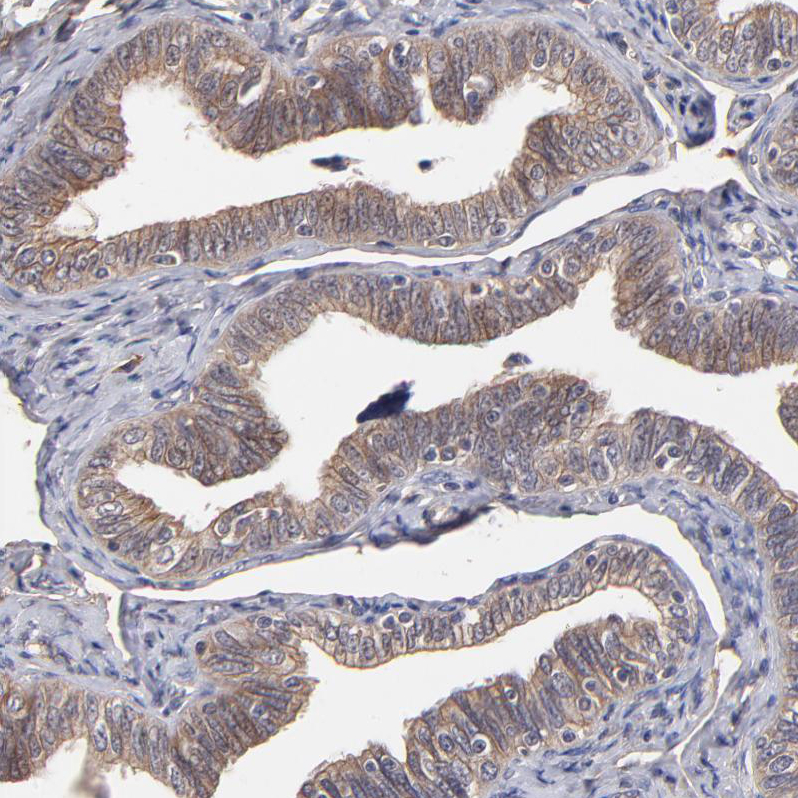

Immunohistochemical staining of human rectum shows strong cytoplasmic positivity in glandular cells.